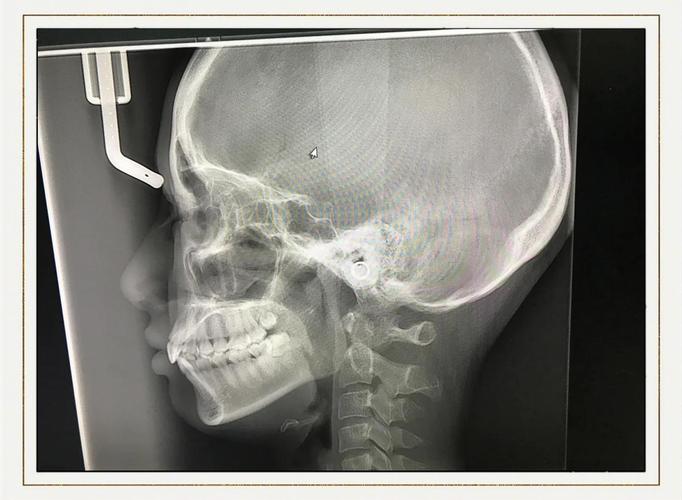

传统矫正检查依赖全景片(曲面断层片)和头颅侧位片,但这两种影像存在局限性:全景片是二维重叠影像,无法清晰显示牙根形态、颊舌侧骨板厚度及邻牙关系;头颅侧位片主要用于测量骨骼和软组织角度,对牙根位置和骨量细节显示不足,而CT通过三维重建,能精准呈现以下关键信息,为矫正提供“导航地图”:

- 颌骨与关节分析:评估颌骨发育情况(如上下颌骨大小、位置关系)、颞下颌关节(TMJ)形态,排除骨性畸形或关节疾病,避免矫正加重关节问题。